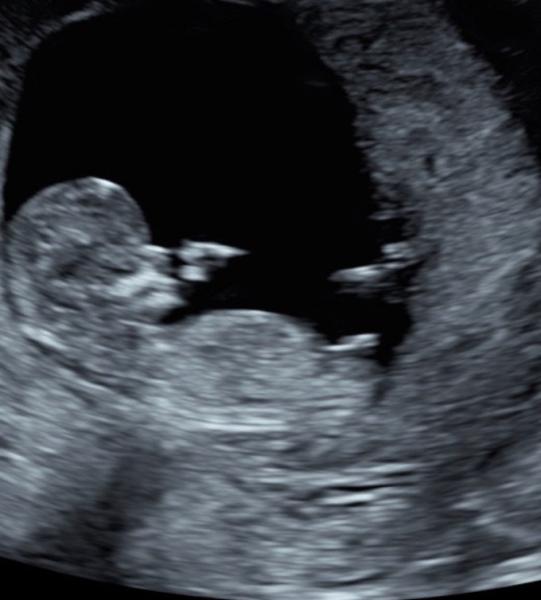

Hallo zusammen, ich würde mich gerne ans Ratespiel hängen. Diese Aufnahme wurde bei der Nackenfaltenmessung 14. Woche (13w0d) gemacht und ihr würde mich über deine und andere Einschätzungen freuen. Danke vorab

Bild zu

Hallo kannst du vill bei mir ein top abgeben :) lg

Bei dir würde ich Mädchen tippen ich befasse mich aber noch nicht lange damit deswegen habe ich hier um andere Meinungen gefragt Es ist wirklich so spannend und aufregend! Das Wichtigste ist natürlich ein gesundes Kind, aber spekulieren darf man ja